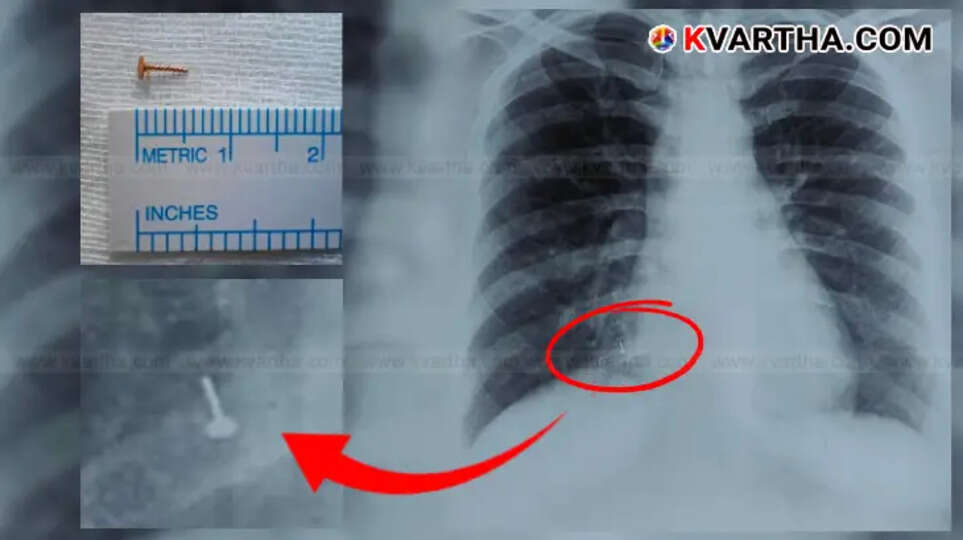

യുവതിക്ക് നടത്തിയ എക്സ്-റേ പരിശോധനയില്, നാല് വര്ഷം മുമ്പ് കാണാതായ മൂക്കുത്തിയുടെ ഒരു ചെറിയഭാഗം വലത്തെ ശ്വാസകോശത്തിന്റെ കീഴ്ഭാഗത്ത് തറച്ചിരിക്കുന്നതായി കണ്ടെത്തി. തുടര്ന്ന് വിദഗ്ധ ചികിത്സയ്ക്കായി യുവതിയെ അമൃത ആശുപത്രിയിലെത്തിച്ചു. അവിടെ റെസ്പിറേറ്ററി മെഡിസിന് വിഭാഗം മേധാവിയായ ഡോ. അസ്മിത മേത്തയുടെ നേതൃത്വത്തിലുള്ള വിദഗ്ധ മെഡികല് സംഘം സങ്കീര്ണമായ ശസ്ത്രക്രിയയിലൂടെ, മൂക്കുത്തിയുടെ ഭാഗം ശ്വാസകോശത്തില് നിന്ന് സുരക്ഷിതമായി നീക്കം ചെയ്തു.

ഈ ശസ്ത്രക്രിയയില്, ശ്വാസകോശത്തിലേക്ക് ഒരു ചെറിയ കാമറയും ഉപകരണങ്ങളും ഉപയോഗിച്ച് കടത്തി, മൂക്കുത്തിയുടെ ഭാഗം കണ്ടെത്തി നീക്കം ചെയ്യുന്ന ഫൈബ്രോടിക് ബ്രോങ്കോസ്കോപി എന്ന മികച്ചൊരു രീതിയാണ് ഡോക്ടര്മാര് സ്വീകരിച്ചത്. രണ്ടു ദിവസത്തെ നിരീക്ഷണത്തിനുശേഷം യുവതിയെ ആശുപത്രിയില് നിന്ന് വിട്ടയച്ചു. ഈ അപൂര്വമായ സംഭവം മേഖലയില് വലിയ ചര്ച്ചയായിട്ടുണ്ട്.